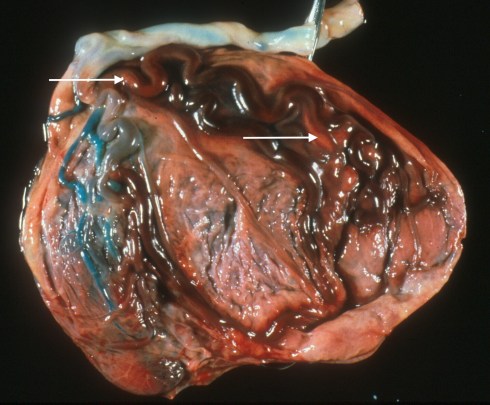

An occlusive thrombus in the umbilical vein would reduce or end oxygenated blood flow to the fetus. I have found such thrombi in stillborn infants but as we will see, there are no criteria to determine if the thrombus was a consequence of umbilical cord compression or the primary event that caused fetal death (Fig 1, 2).

Fig 1a: The cord insertion has been cut and the dilated vein demonstrated thrombus at the arrow. This stillborn infant had meconium staining and aspiration.

Fig 1b: This photograph of the sliced placenta on its side also shows the section of thrombosed umbilical vein (arrow).